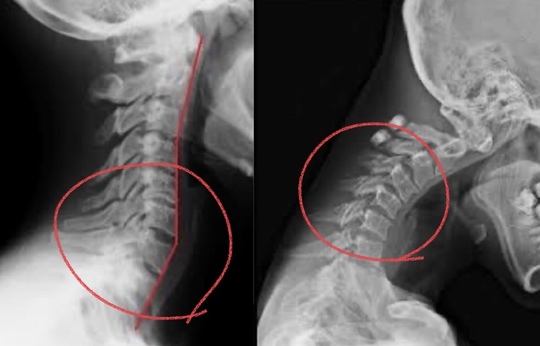

写真の〇の部分をみてわかるように、「ココが動いている!」事がわかると思います。

これが過剰に動く場所になります。

この過剰に動く場所で痛みを出し、痛いことにより患部を守るために筋が収縮して守ろうとする。

これがコリの発生原因です。